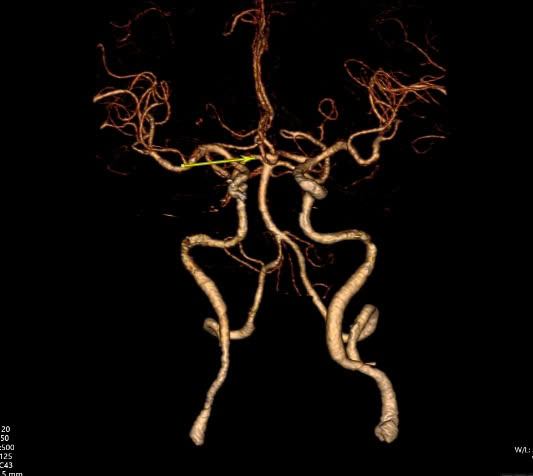

Ngay khi tiếp nhận, các bác sĩ đã chụp CT não có dựng hình mạch máu để kiểm tra thì phát hiện tình trạng xuất huyết khoang dưới nhện do vỡ phình mạch máu ở đoạn động mạch não thông trước, kích thước túi phình lớn nhất là khoảng 7mm và có nhiều múi.

Để xử lý bệnh cảnh này, các bác sĩ khoa Sọ Não Cột Sống 2 đã quyết định phẫu thuật kẹp cổ túi phình nhằm loại trừ túi phình ra khỏi hệ thống mạch máu và ngăn tình trạng xuất huyết não tái phát về sau.

ThS. BS. Lê Tấn Linh – Khoa Sọ Não Cột Sống 2, người trực tiếp thực hiện ca mổ, chia sẻ: "Cả 3 bệnh nhân đều được phẫu thuật vi phẫu kẹp cổ túi phình mạch máu não bằng phương pháp mở sọ vùng trán thái dương.

Dưới sự hỗ trợ của kính hiển vi, các bác sĩ tiến hành bộc lộ cổ túi phình để đặt clip ngang cổ phình mạch và loại bỏ túi phình ra khỏi hệ thống mạch máu não mà không ảnh hưởng dòng máu nuôi não. Sự hỗ trợ của kính vi phẫu giúp phẫu thuật viên thao tác nhẹ nhàng, tinh tế, hạn chế tác động mạnh dẫn đến nguy cơ xuất huyết trong lúc mổ."